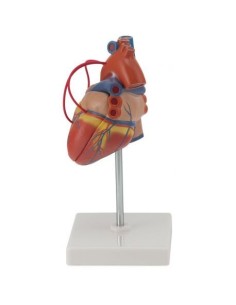

Dal cranio in 22 parti con incastri magnetici ai modelli di colonna vertebrale, da quelli di articolazioni a quelli di cuore, ogni pezzo della nostra collezione è progettato per un’immersione totale nello studio dell’anatomia umana. I nostri modelli, realizzati tramite scansioni di ossa vere, garantiscono un’esperienza tattile autentica e una fedeltà di peso quasi identica agli originali.